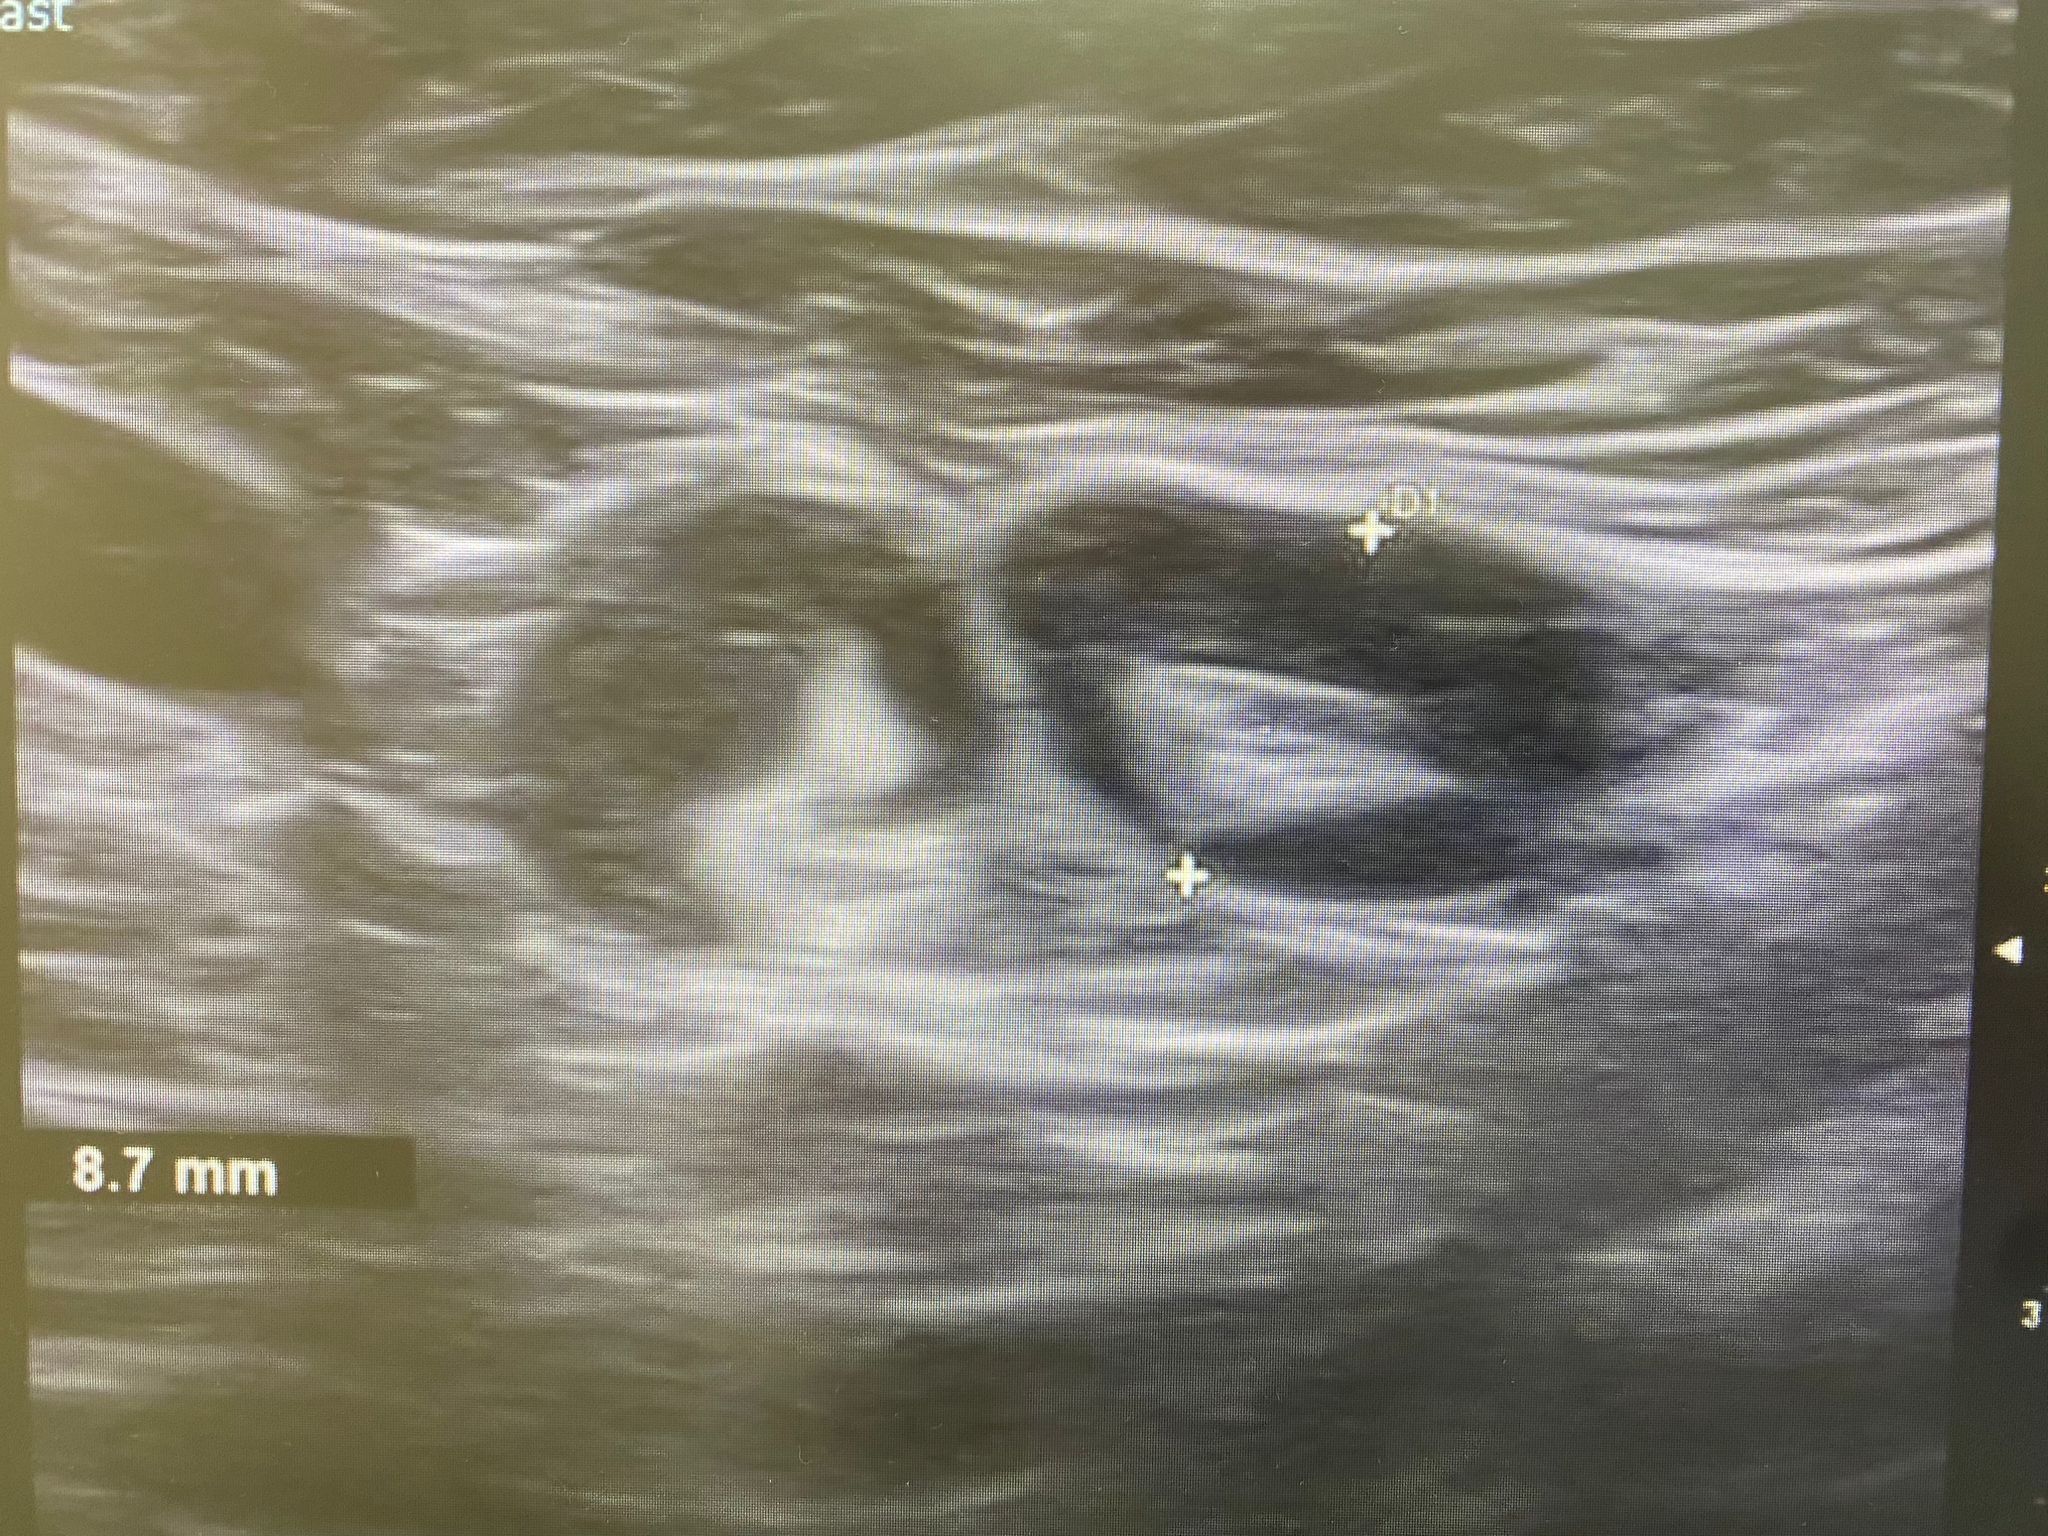

Ecografía: Valoración de adenopatías para acercamiento diagnóstico (típicas/atípicas).

Adenopatías patológicas, algunas redondeadas, con eje anteroposterior > 1 cm, parénquima homogéneo, cortical engrosada aunque con hilio respetado.

Ecografía axilar: múltiples adenopatías con eje corto > 2 cm y cortical engrosada.